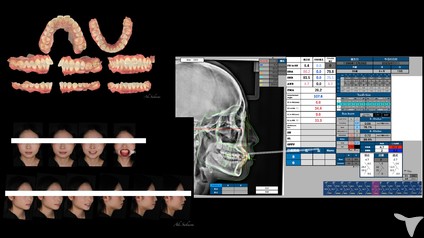

・セファロ(矯正歯科専用の顔の骨格を調べるレントゲン装置)

患者様の治療の経過を写真などで記録として残すことを徹底しています。

治療の経過をしっかりと追うことができますので、着実に研鑽を積むことができます。